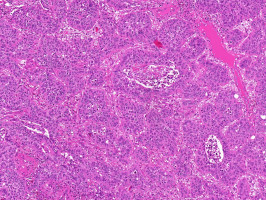

The multicenter study analysed nearly 2,000 digitised tissue slides from colon cancer patients across seven independent cohorts in Europe and the US. The samples included both whole-slide images of tissue samples and clinical, demographic, and lifestyle data. The researchers developed a novel “multi-target transformer model” to predict a wide range of genetic alterations directly from routinely stained histological colon cancer tissue sections. Previous studies were typically limited to predicting single genetic alterations and did not account for co-occurring mutations or shared morphological patterns.

“Earlier deep learning models and analyses of the underlying tissue alterations have generally focused on only a single mutation at a time. Our new model, however, can identify many biomarkers simultaneously, including some not yet considered clinically relevant. We were able to demonstrate this in several independent cohorts. We also observed that many mutations occur more frequently in microsatellite-instable tumours (MSI),” explains Marco Gustav, M.Sc., first author of the study and researcher at EKFZ for Digital Health at TU Dresden. Certain types of colorectal cancer can be classified based on microsatellite instability (MSI). Microsatellites are short, repetitive DNA sequences spread throughout the genome. In cancer, MSI can occur when these sequences become unstable due to defects in the DNA repair system. MSI is an important biomarker for identifying patients who may benefit from immunotherapy. ”This suggests that different mutations collectively contribute to changes in tissue morphology. The model recognises shared visual patterns, rather than independently identifying individual genetic alterations,” he adds.

The researchers demonstrated that their model matched and partly exceeded established single-target models in predicting numerous biomarkers, such as BRAF or RNF43 mutations, and microsatellite instability (MSI) directly from pathology slides. The pathological expertise required to assess tissue changes from histological slides was provided by experienced medical specialists. Dr. Nic Reitsam from the University Hospital Augsburg played a key role in the study.